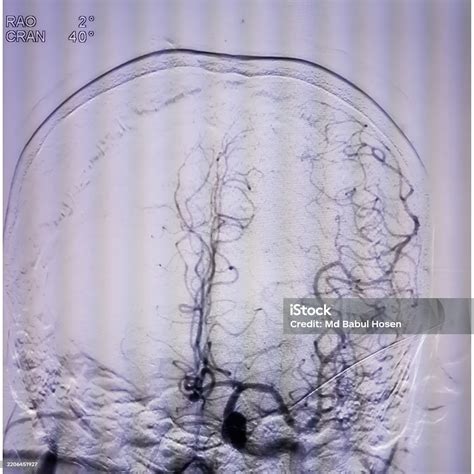

At its core, Digital Subtraction Angiography is a fluoroscopic technique that uses a computer-aided process to subtract the background image from a subsequent image taken after the injection of a contrast agent. The process begins with a "mask" image, which captures the anatomy of the target area without any contrast. Once the radiopaque contrast dye is injected into the bloodstream, a second set of images is captured. The computer then mathematically subtracts the mask from the contrast-filled images, leaving only the opacified vessels visible on the screen.

This process effectively removes visual "noise," allowing interventional radiologists to see even the smallest branches of an artery. Because of its superior contrast sensitivity and spatial resolution, it remains the preferred method for assessing conditions like aneurysms, stenosis, and arteriovenous malformations.

• Cerebrovascular Imaging: Used extensively to map the blood supply to the brain, helping detect aneurysms, carotid artery stenosis, or ischemic strokes.